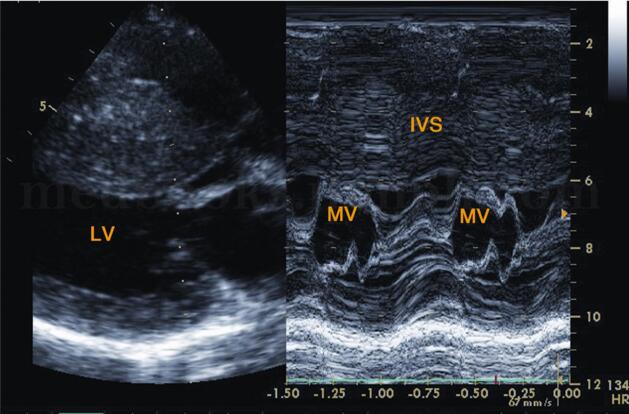

超声图片 如图2‐1‐196,图2‐1‐197。

超声描述 左房轻度增大,室间隔呈团块状明显增厚(39.7mm),左室后壁轻度增厚(11.4mm),两者之比>1.5∶1,呈非对称性;室间隔回声增粗明显不均,呈毛玻璃样改变;二尖瓣水平M型见二尖瓣前叶EF斜率下降,E峰与室间隔相碰,SAM现象(+);左室流出道狭窄,其内收缩期充满花彩血流束,射流流速3.56m/s,压差50.7mmHg。

图2‐1‐196 左室长轴切面左房增大,室间隔明显增厚,左室后壁厚度正常范围

图2‐1‐197 二尖瓣波群M型超声左室流出道梗阻时二尖瓣C‐D段收缩期前向运动,呈多层弓背样隆起,即SAM现象